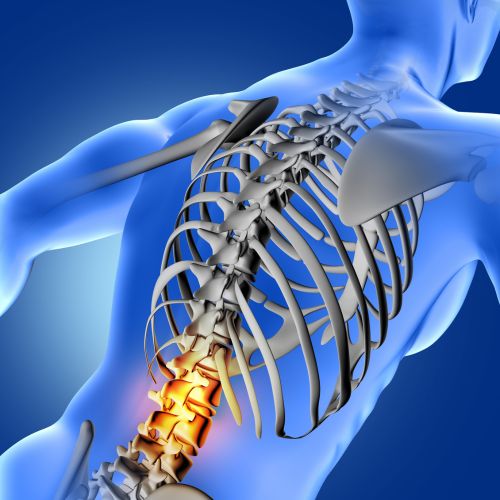

Y a-t-il des contre-indications à l'utilisation de vos coussins ?

Nos produits sont sans risque pour la majorité des utilisateurs.

Toutefois, en cas de conditions médicales spécifiques, consultez votre médecin avant l'utilisation.